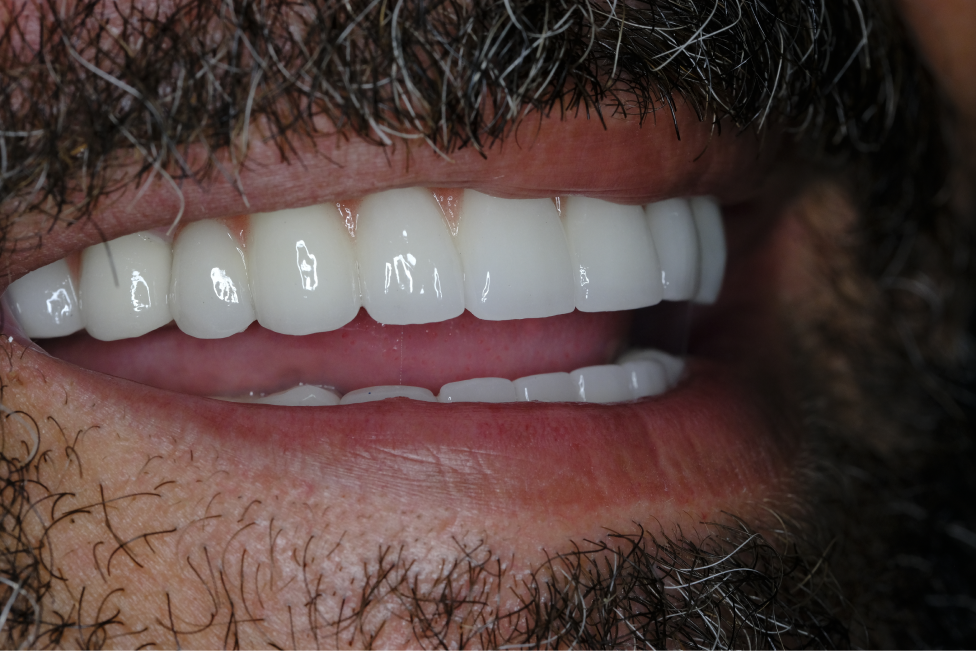

Three months later, after the completion of implant osseointegration, the patient's need for prostheses was evaluated. Zirconium prostheses were preferred to meet the patient's aesthetic and functional requirements. Zirconium prostheses offer advantages in terms of durability and natural appearance.

The application of Naxis implants and zirconium prostheses, taking into account the patient's specific conditions, resulted in a successful treatment outcome. This approach may provide a reliable option for implant treatment in patients with periodontal problems or systemic health issues.